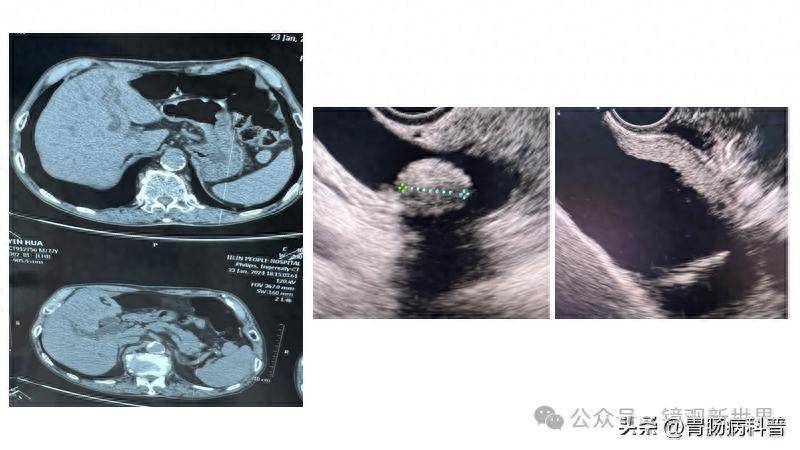

男,43岁,右上腹痛,murphy征阳性,皮肤,巩膜无黄染,影像检查如图,最

图片尺寸364x544